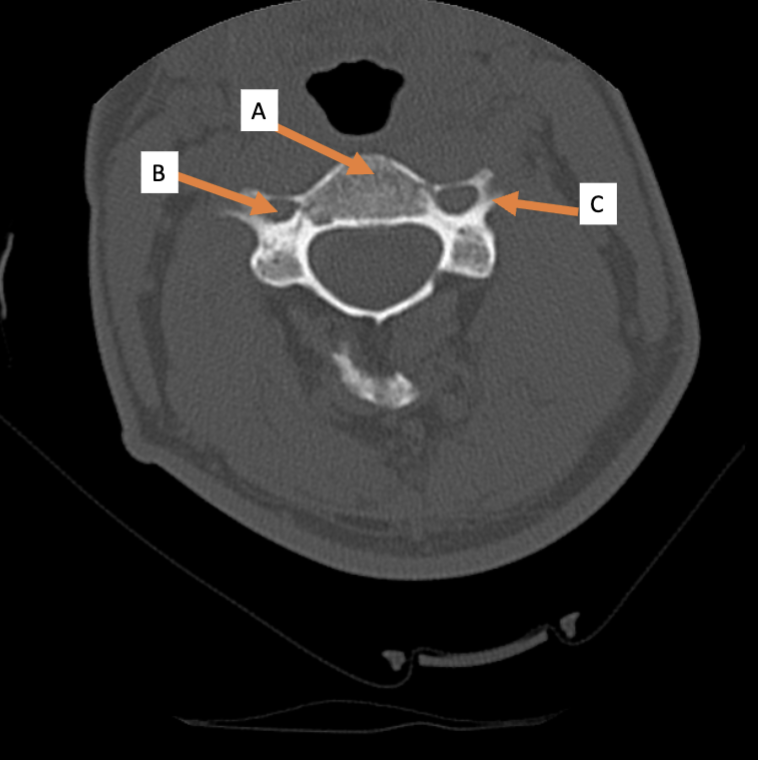

A. Identify structure

Transverse foramen; Vertebral a.

B. Identify structure; What goes through this feature?

Transverse process

C. Identify structure